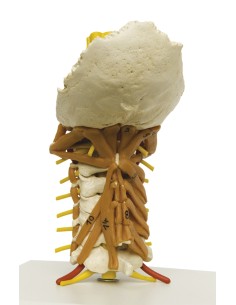

3B Scientifique, Colonne vertébrale de luxe peinte de façon classique avec troncs de...

Du crâne en 22 parties à verrouillage magnétique aux modèles de colonne vertébrale, des modèles d'articulation aux modèles de cœur, chaque pièce de notre collection est conçue pour une immersion totale dans l'étude de l'anatomie humaine. Nos modèles, réalisés à partir de scans d'os réels, garantissent une expérience tactile authentique et une fidélité de poids presque identique aux originaux.

Indispensables aux étudiants comme aux professionnels, nos modèles anatomiques sont des outils pédagogiques qui permettent d'observer les structures anatomiques avec précision, en évitant les dissections ou les études invasives. Ils sont également utiles pour expliquer les pathologies aux patients, ce qui rend la communication plus efficace et permet de gagner un temps précieux.